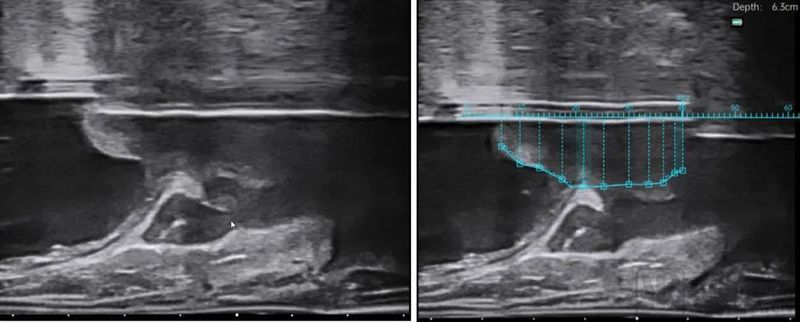

水刀机器人手术是第一个把智能影像术中超声影像引入到BPH手术中的术式。水刀手术机器人,也就是智能影像引导高能水射流自主手术机器人,会根据前期医生的在术中的全局规划,在影像导航的指引下,自动控制水刀精准切除。学习曲线短,对医生本身的经验和手术技巧要求较低,医生所要学习的就是如何通过影像规划手术靶区。由于水刀手术机器人是冷切割,从根本上避免了一切热损伤的可能性和各种各样的误操作,在保证有效性的基础上,更安全、更温和。

图片

水刀手术机器人影像照片